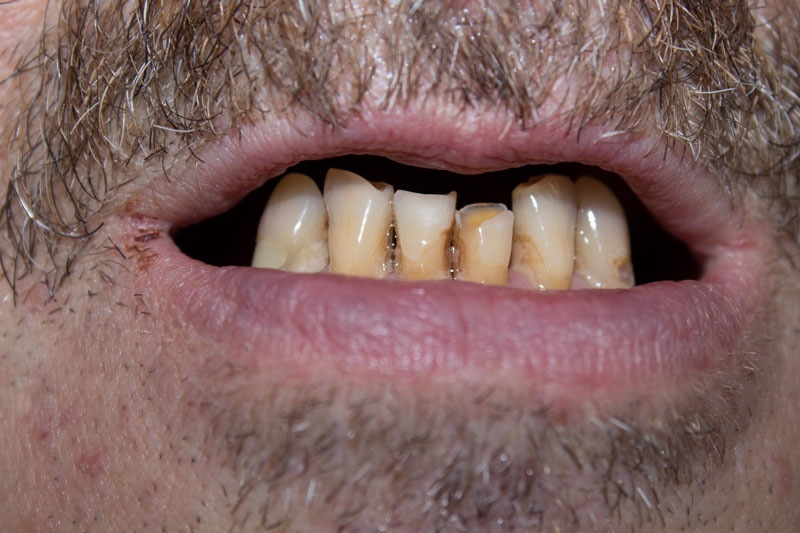

Полное отсутствие зубов на верхней и частичное на нижней челюсти. Неудовлетворительная эстетика оставшихся зубов. Эмоциональный дискомфорт из-за отсутствия зубов.